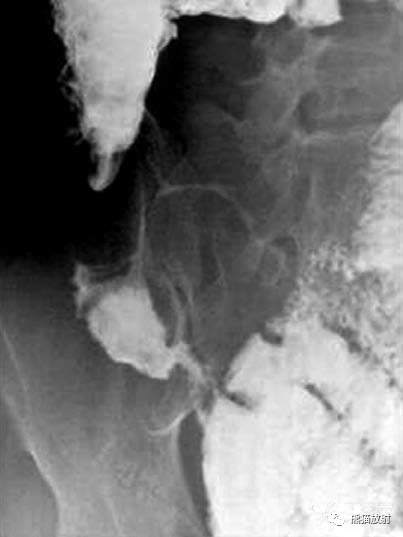

Fleischner征:回盲瓣增厚伴回肠末端狭窄;CT示回肠末端狭窄伴瓣膜区增厚。

回盲部的早期受累是明显的痉挛和运动亢进伴瓣膜水肿。回盲瓣唇增厚和/或张开瓣膜,末端回肠 ( Fleischner或“倒置伞”征) 被认为是结核的特点。

回盲部肠腔持续性狭窄

盲肠短缩伴末端回肠悬吊

回盲部环形缩窄